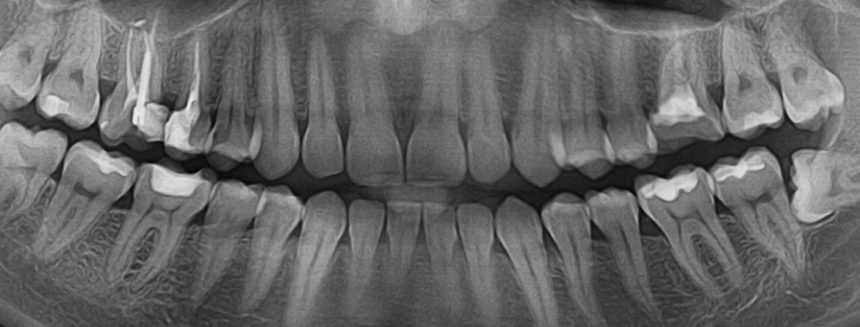

Компьютерная томография челюстно-лицевого отдела (снимок зубов в формате 3D) – это современный метод обследования основных параметров челюстного отдела.

Чтобы определить все возможные типы и виды имплантации, пациенту необходимо пройти компьютерную 3D томографию челюстно-лицевого отдела, а данные переслать нам. Необходимо, чтобы компьютерная томография была сделана в одной из нижеуказанных программ. Данные программы имеют сертификат РБ и мы работаем в частности с: